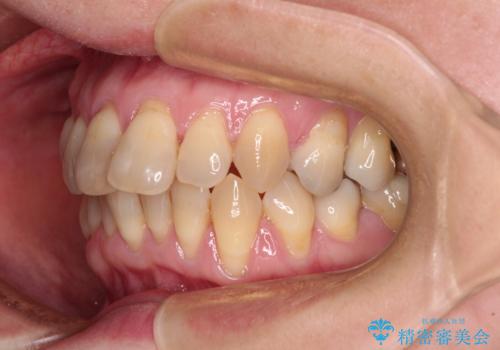

- 上下前歯のデコボコと、奥歯の銀歯を気にして来院された患者様です。

仕事柄あまり目立つ装置は付けることは避けたいとのことで、インビザラインによるマウスピース矯正を行うこととしました。

概ね歯列が整ったところで銀歯の全てをセラミッククラウンなどに置き換え、その後インビザラインを1セット使用して仕上げていくこととしました。